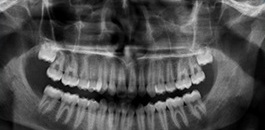

Exame realizado em apenas 17 segundos. Nosso equipamento permite a combinação de 9 diferentes tipos de arcadas, permitindo imagens nítidas e com altíssima definição.

Muito utilizado para avaliação dos seios da face. Através do software romexis, podemos utilizar as ferramentas de inversão de imagem, brilho e contraste para uma avaliação mais precisa.